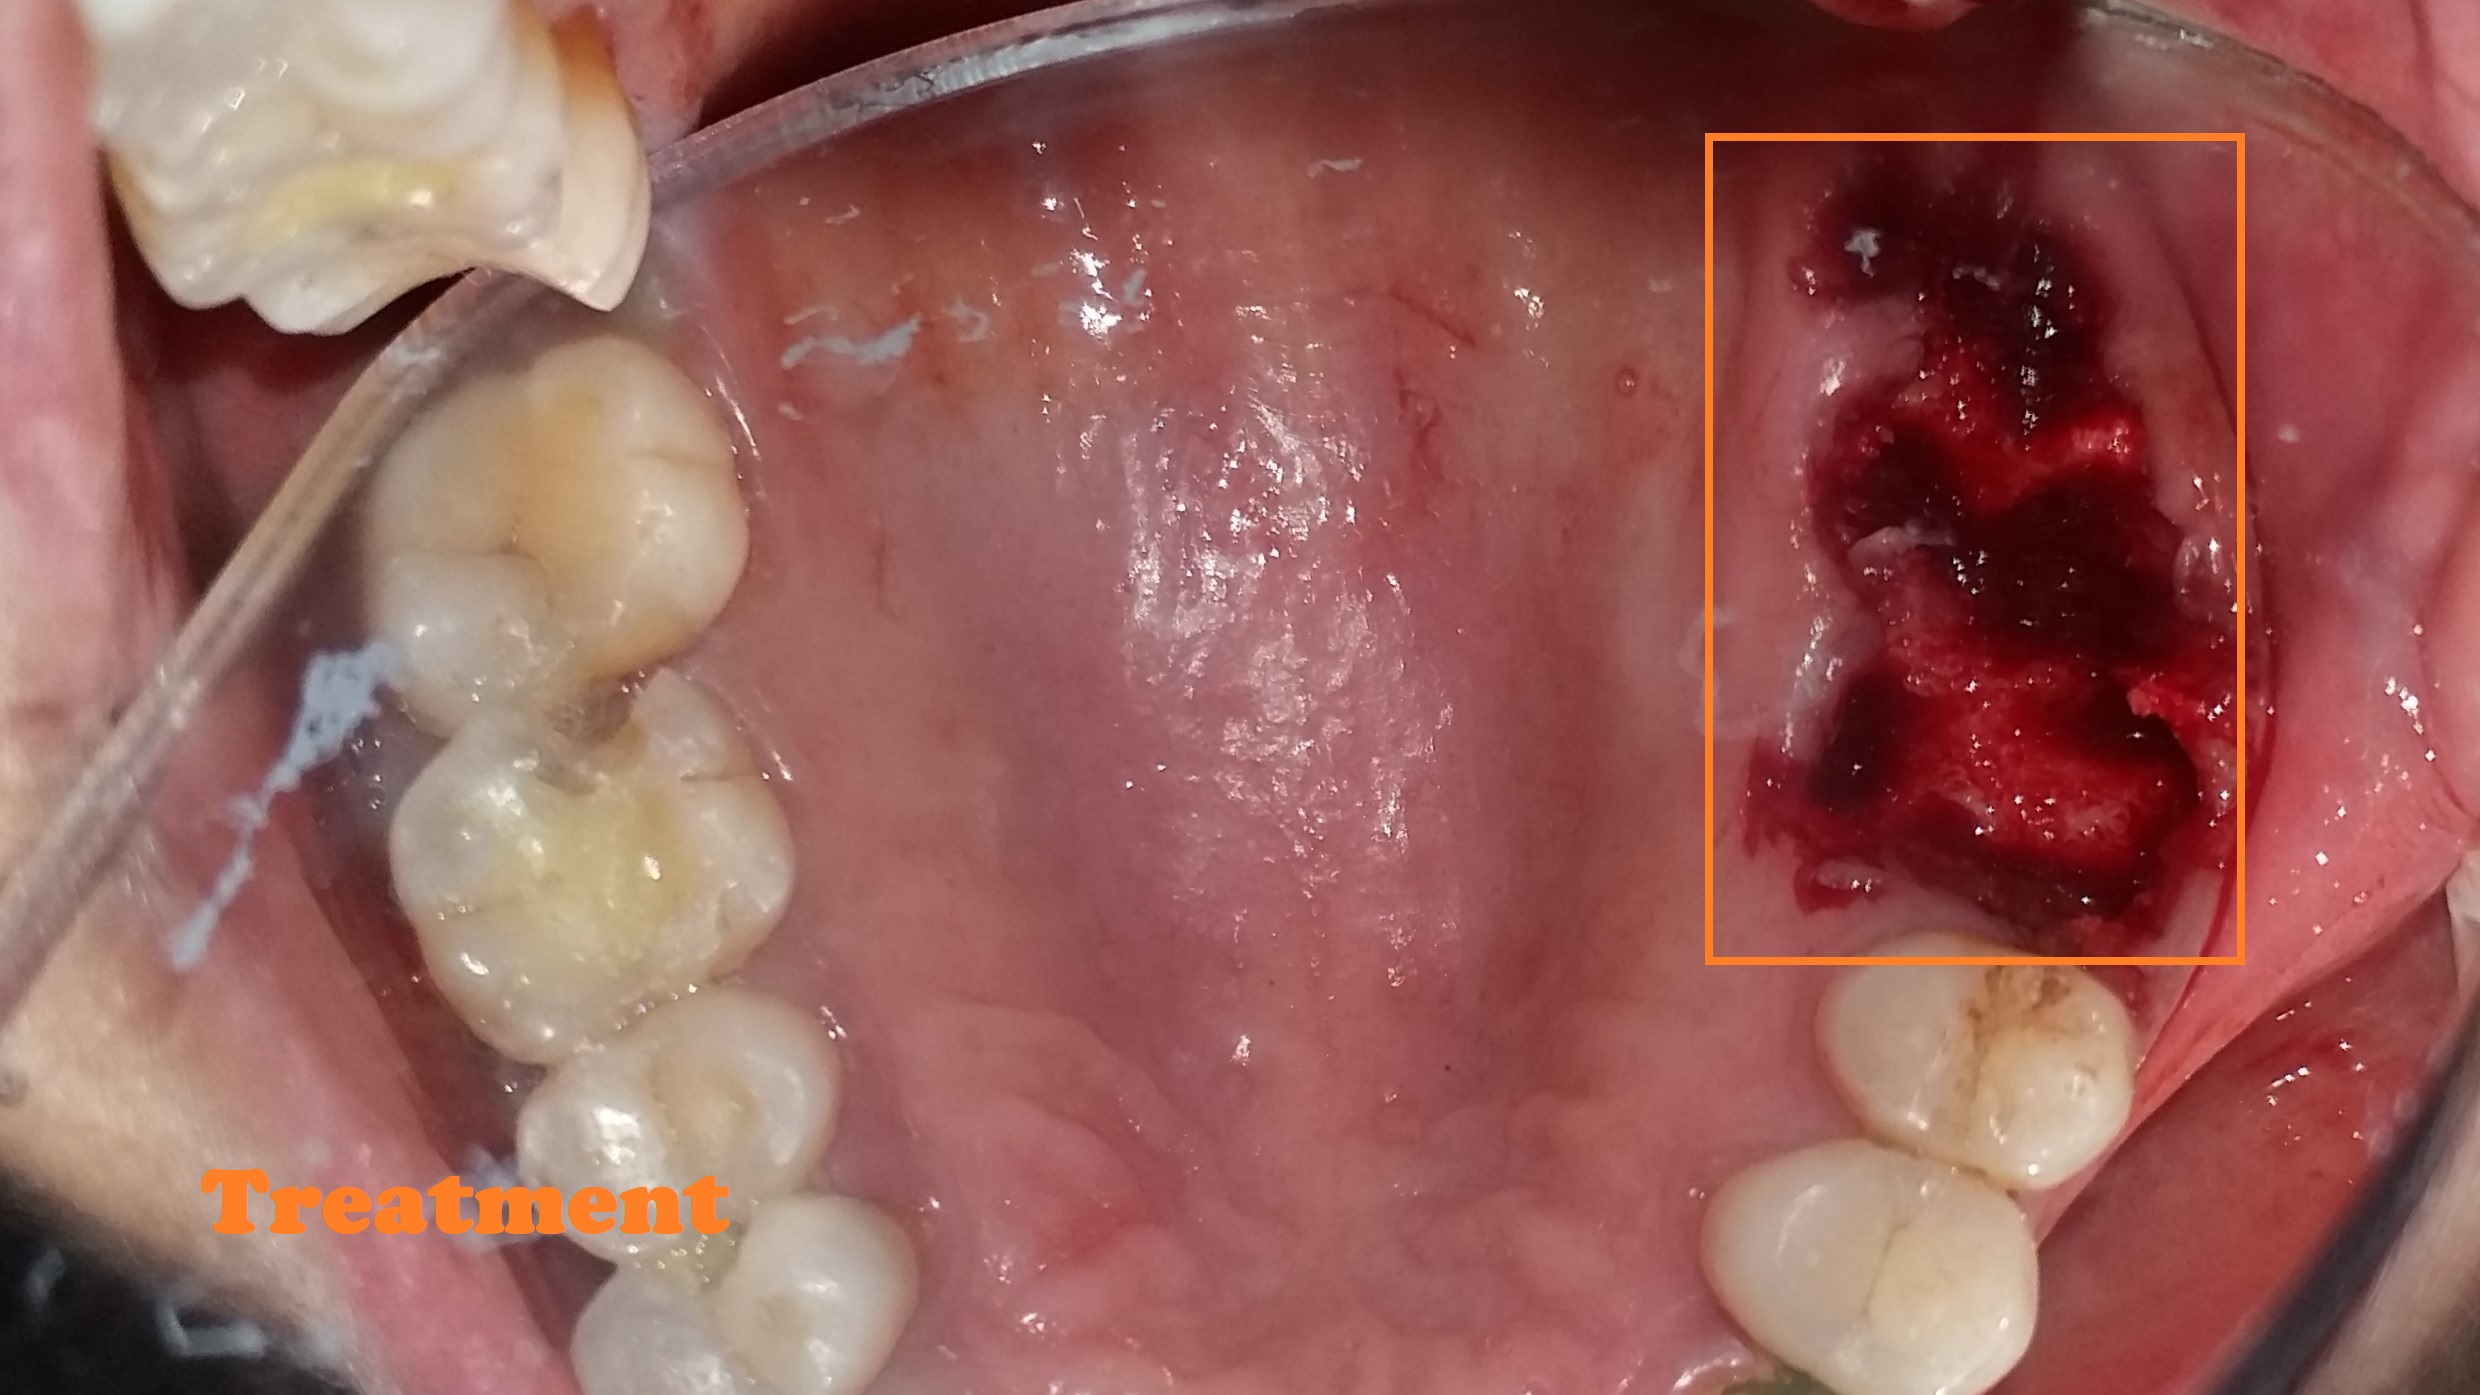

- Removes infected nerve tissue while preserving your natural tooth.

- Relieves pain, swelling, and sensitivity caused by deep decay or infection.

- Protects against tooth extraction and maintains natural biting ability.